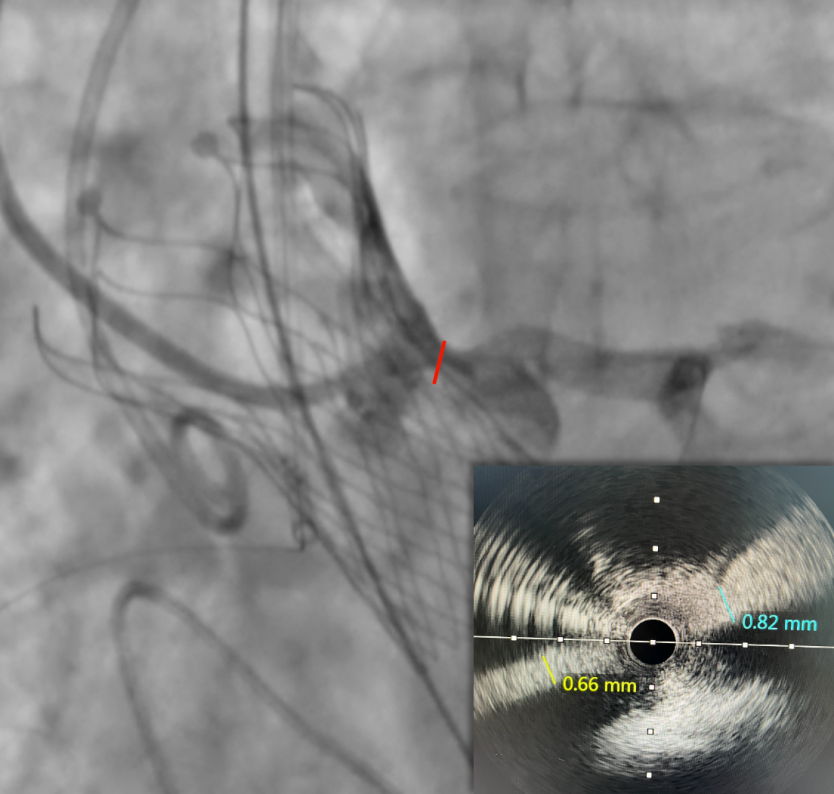

IVUS检查冠脉开口,

进一步精准评估冠脉开口遮挡情况

IVUS检查提示因原瓣叶遮挡,左冠开口受阻,最窄处残余缝隙0.66-0.82mm。

左冠植入4.0x19mm冠脉开窗支架

5.0mm球囊后扩张支架近段

复查左冠开口面积恢复至12.76mm2

术后经导管同步测压,跨瓣压差由70mmHg,改善至术后0mmHg。经食道超声显示VitaFlow®瓣膜位置固定,无瓣周漏,瓣膜形态良好。再次通过IVUS评估左侧冠脉开口面积恢复至12.76mm2,患者生命体征平稳并监护。